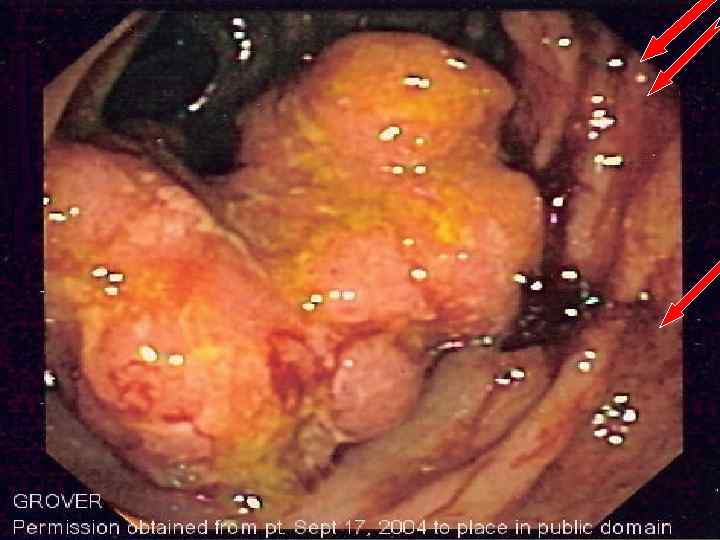

РАК ТОЛСТОЙ КИШКИ

РАК ТОЛСТОЙ КИШКИ

РАК ТОЛСТОЙ КИШКИ

РАК ТОЛСТОЙ КИШКИ